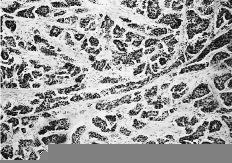

Las cuatro observaciones mostraron positividad a los RE con histocores superiores a 100. La evaluacion inmunomorfológica de los RE arrojó cifras de histocore hormonal (HH) comprendidas entre 108 y 300, con intensidades de ++/+++, en un porcentaje celular comprendido entre el 36 y el 75% (Figs. 1 y 2). La positividad a los RE se manifestaba por la presencia de inmunotinción especifica nuclear. En general, la positividad a los RE mostró un carácter de heterogeneidad de forma que no todas las áreas tumorales presentaban el mismo nivel de positividad o bien existían diferentes porcentajes en el número de núcleos marcados. En dos casos existían en periferia a las áreas tumorales imágenes de ginecomastia proliferativa, que asimismo mostraba positividad al receptor estrogénico (Fig. 3). En un caso (HH de 108) asimismo se cuantificaron en 230 fmol/mg ADN los REn mediante el método bioquímico DCC.

Fig. 2. Imagen microscópica del componente intraductal de uno de los casos estudiados mostrando positividad nuclear para los REn con un carácter heterogéneo. (ERICA, 400*.)